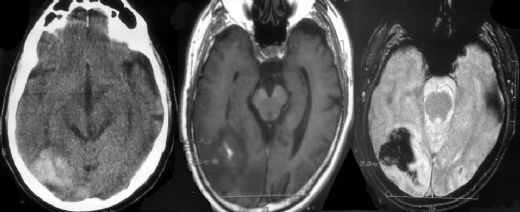

Beyin kanaması, beynin içindeki kan damarlarının yırtılması veya sızması sonucu ortaya çıkan ciddi bir sağlık durumudur. Bu durum, beyin dokusuna zarar verebilir ve çeşitli nörolojik komplikasyonlara yol açabilir. Beyin kanamasının belirtileri arasında baş ağrısı, bulantı, kusma, bilinç kaybı ve nörolojik işlevlerde bozulma yer alır. Ancak, bu durumun ateş ile ilişkisi üzerine çeşitli tartışmalar mevcuttur. Beyin Kanamasının NedenleriBeyin kanaması, birçok faktörden kaynaklanabilir. Bunlar arasında:

Belirtilerin hızlı bir şekilde değerlendirilmesi, acil tıbbi müdahale gerektiren bir durum olduğunun göstergesidir. Tıbbi Müdahale ve Tanı SüreciBeyin kanaması şüphesi durumunda, hastanın acil servise başvurması önemlidir. Tanı süreci genellikle şu adımları içerir:

Bu süreç, doğru tanı ve uygun tedavi için kritik öneme sahiptir. Tedavi SeçenekleriBeyin kanaması tedavisi, kanamanın türüne, büyüklüğüne ve hastanın genel sağlık durumuna bağlı olarak değişir. Tedavi seçenekleri arasında: